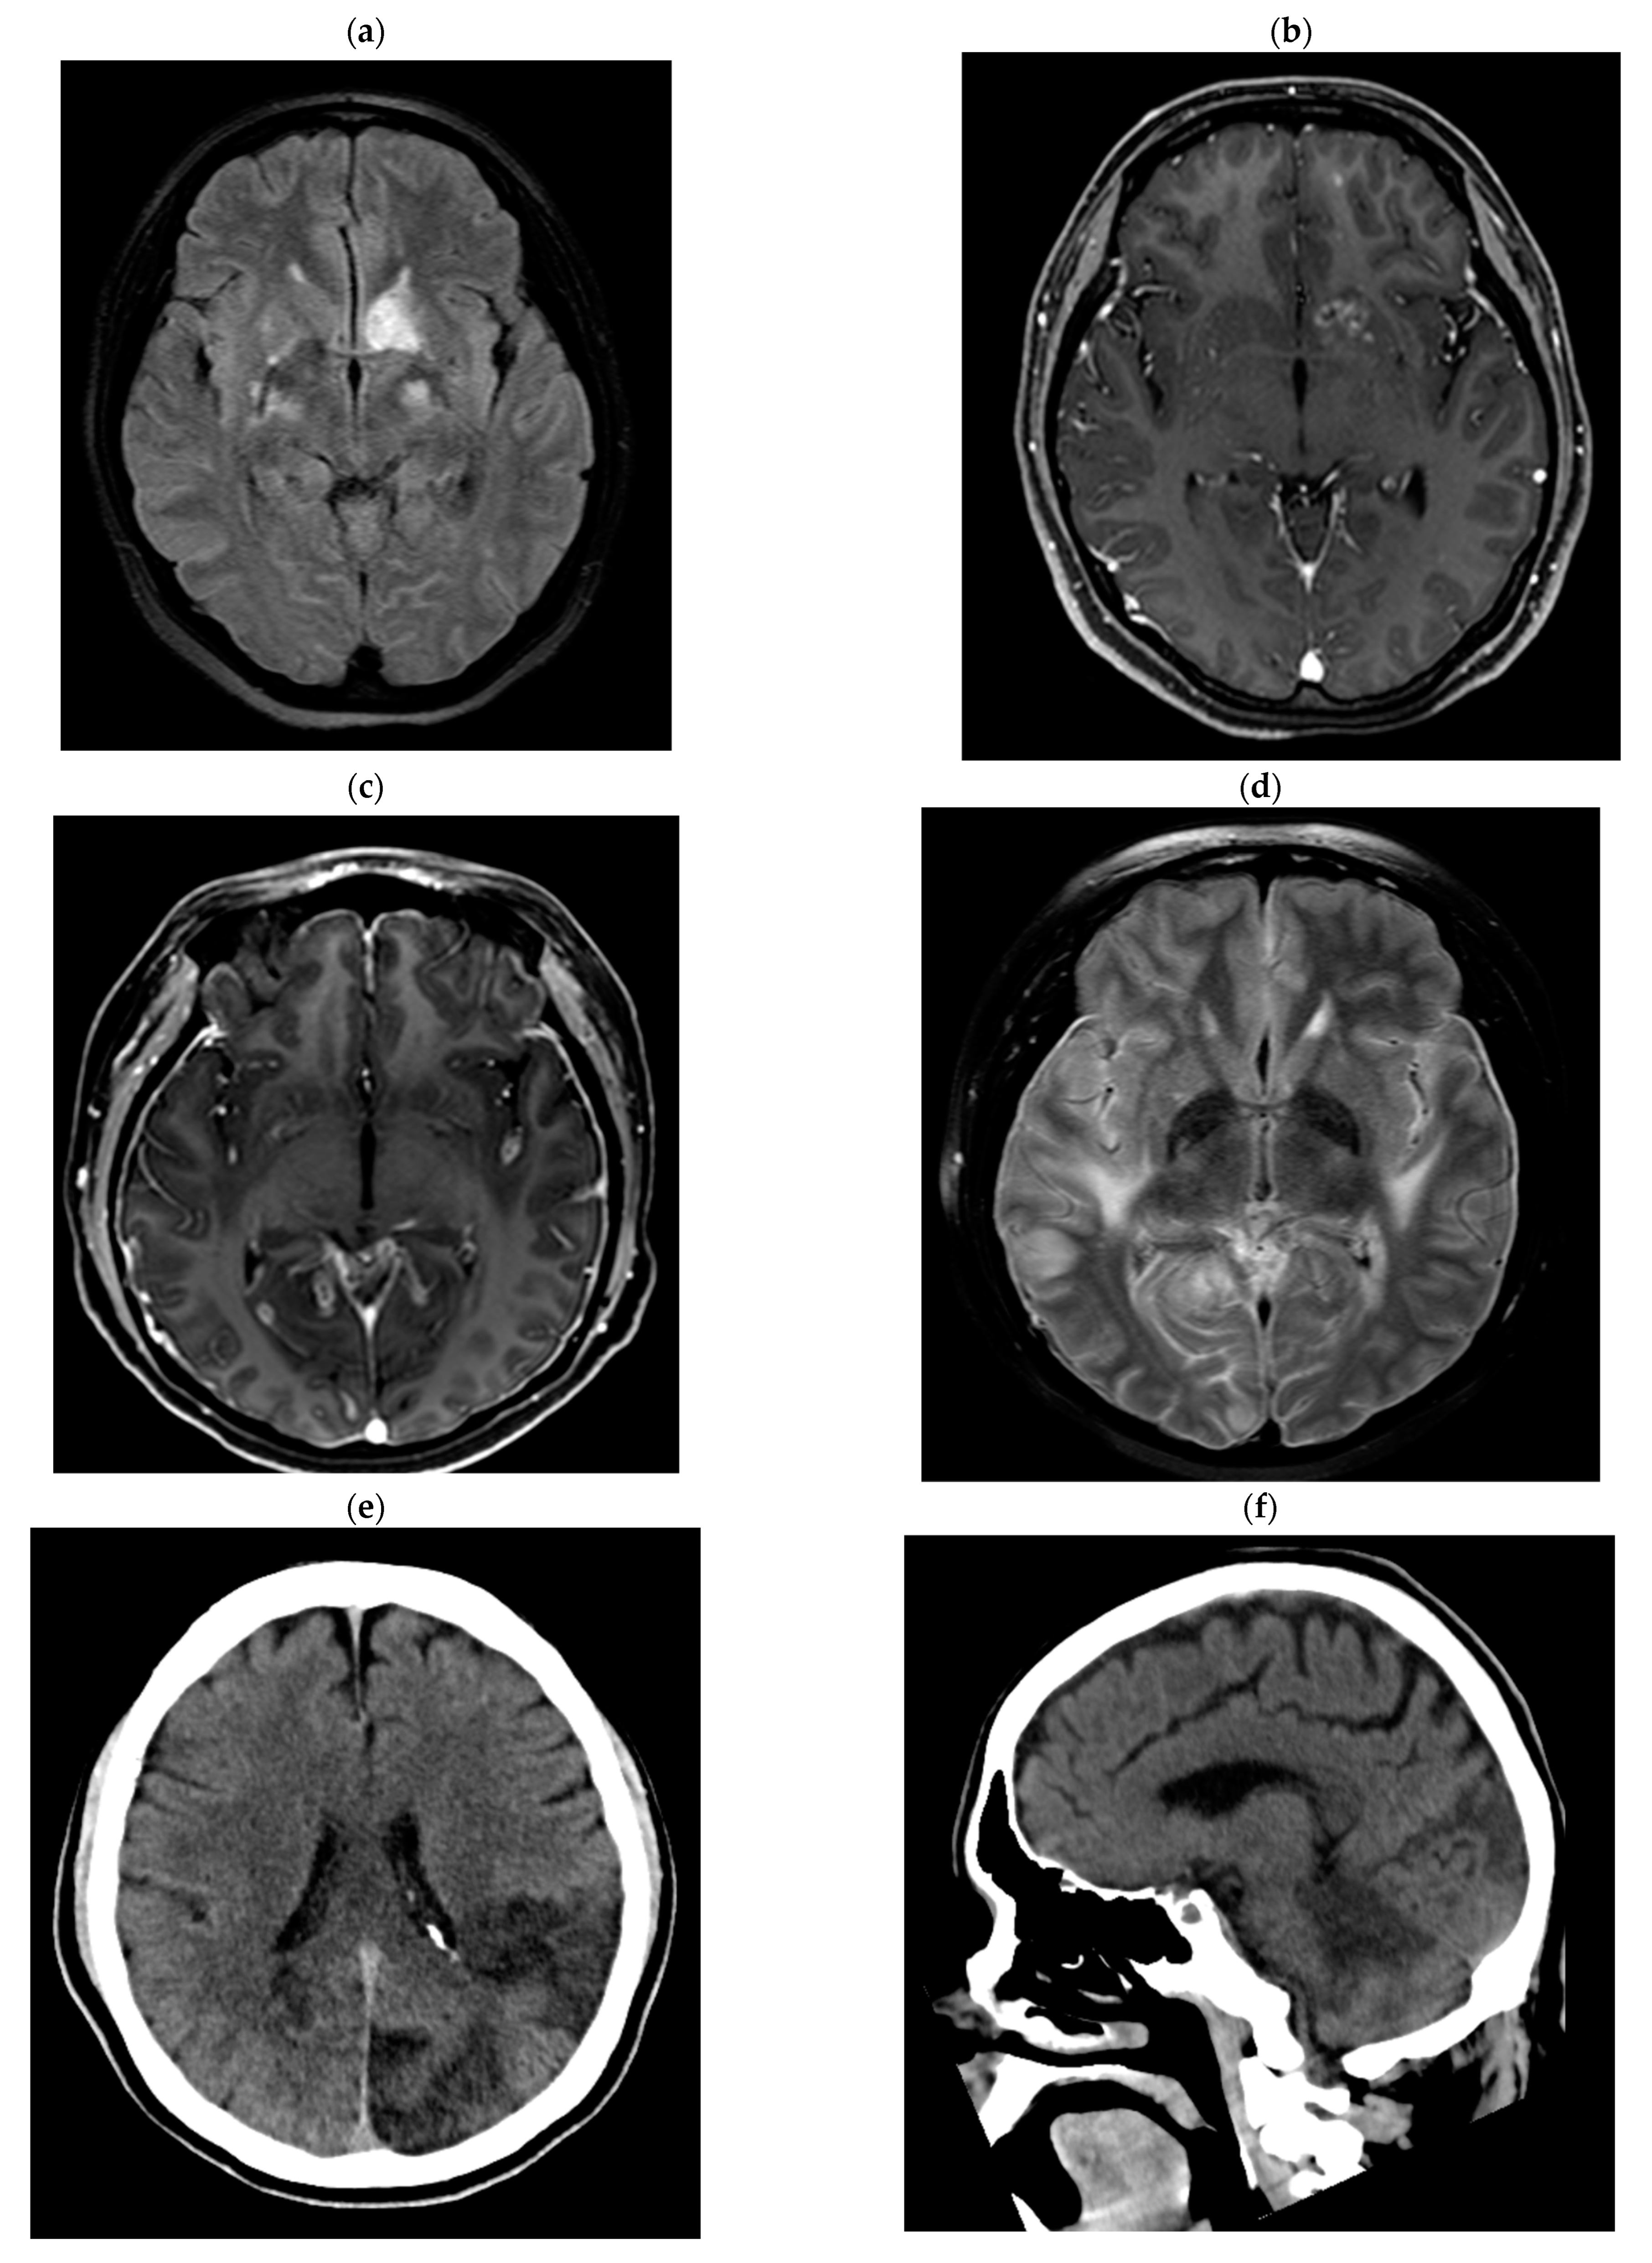

2.2. Detailed Case Descriptions